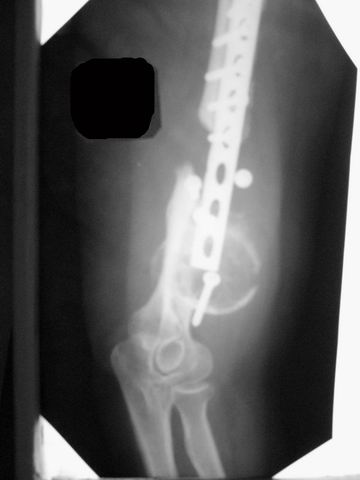

[Ortho] ложный сустав после остеосинтеза плеча

Уважаемые коллеги! Обратилась женщина 38 лет, соматически здорова, ORIF наружным доступом в 2005 году (к сожалению снимки пока не нашли), перелом типа В1. После остеосинтеза никуда не обращалась. Летом прошлого года (через 2 года после операции) во время перетаскивания стиральной машины появились боли в оперированном плече, но пришла лишь сейчас. Клинически: варусная деформация, патологическая подвижность, объем движений в локтевом суставе почти полный, неврологических расстройств нет, признаков инфекции нет. Коллеги, как вы думаете, возможно ли срастить данный неоартроз? Микрохирургия  недоступна. Честно говоря, не встречаясь с такими последствиями никогда ранее, надеюсь на помощь "коллективного разума".

Имя     : плечо L.jpg